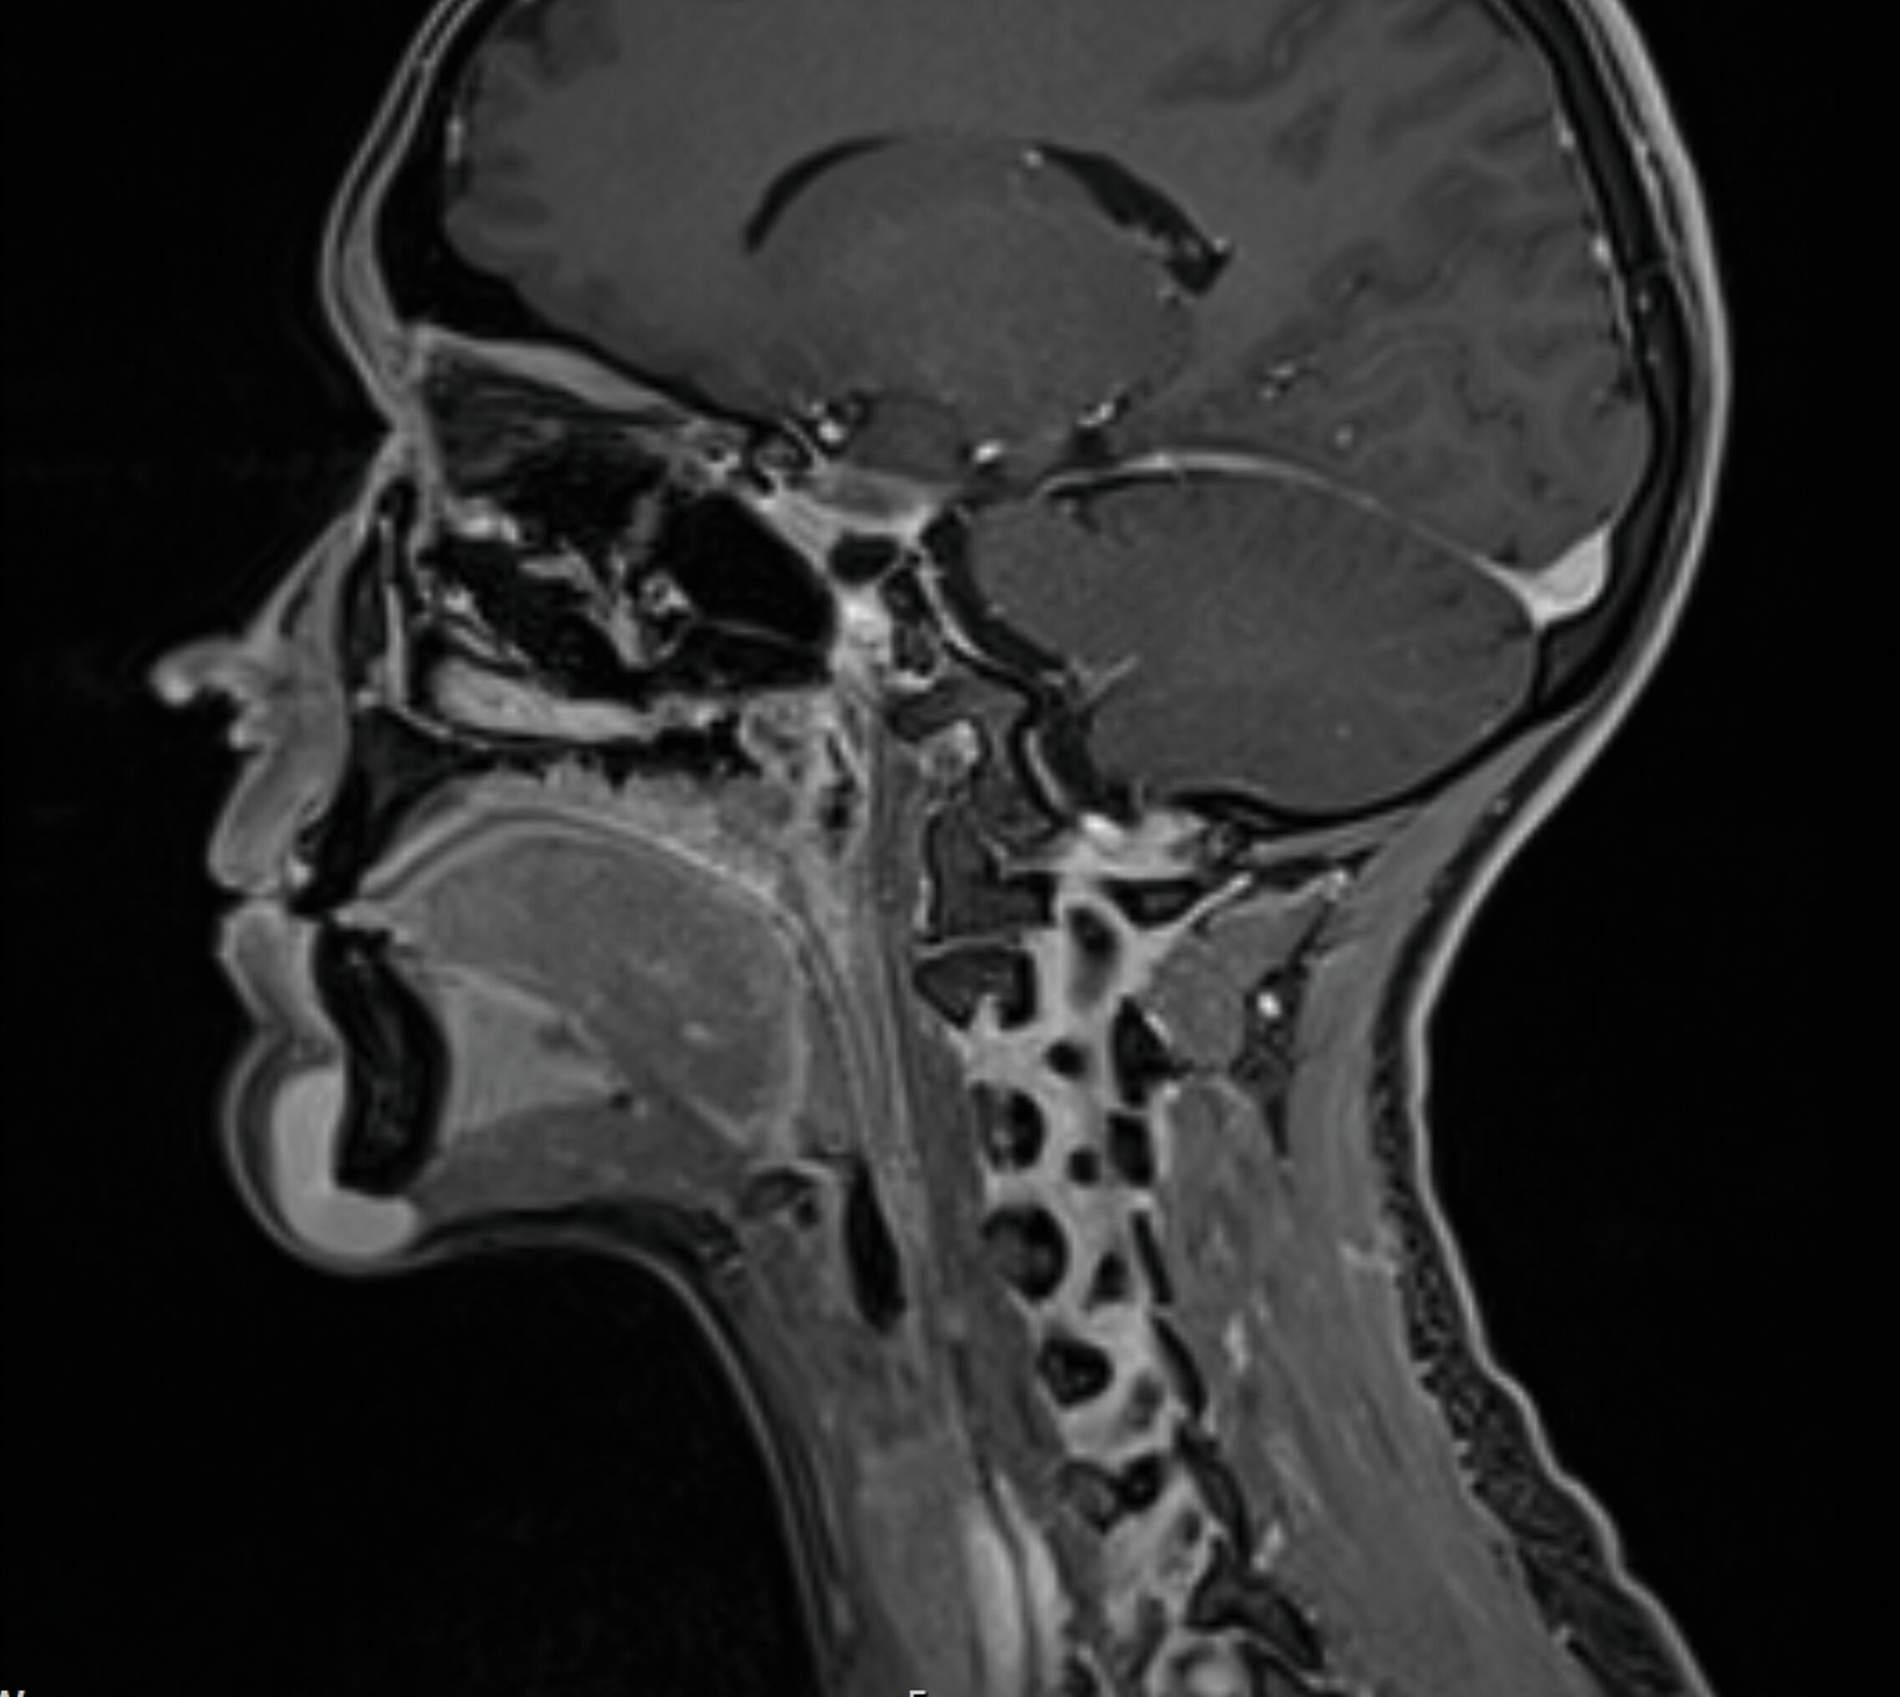

Eine Unterbrechung der Kortikalis oder Abszessformationen ergaben sich nicht. Zur erweiterten Diagnostik erfolgte die Anfertigung einer Magnetresonanztomografie des Kopf-Hals-Bereichs. Hier zeigte sich bildmorphologisch ein zur Muskulatur isointenser Tumor mit deutlicher Kontrastmittelaufnahme, den Unterkiefer basal teilweise umschlingend, jedoch nicht destruierend (Abbildungen 3 und 4).